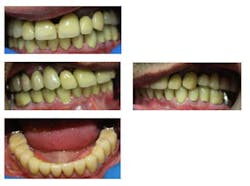

Fig. 10: Inserted full-coverage PFMs

Upon completion, a maxillary day and night guard was fabricated for the patient, and he was advised to constantly wear this device.